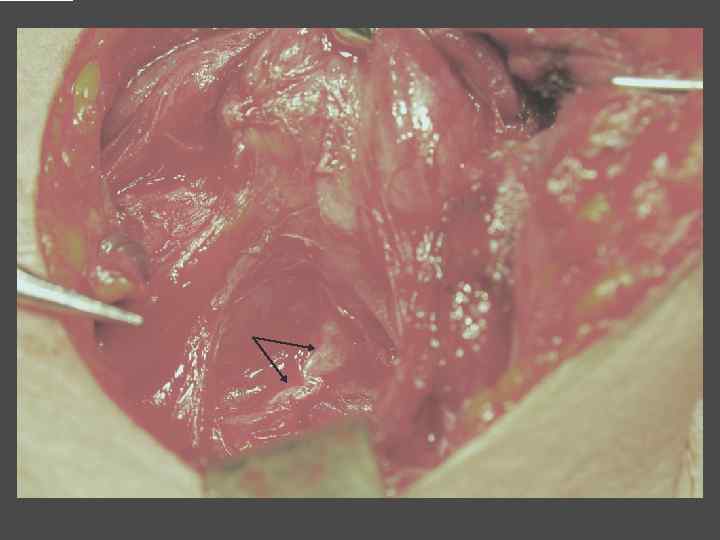

ОСЛОЖНЕНИЯ ХИРУРГИЧЕСКОГО ЛЕЧЕНИЯ ►Поражение возвратного нерва, приводящее к параличу голосовой связки на стороне поражения, как следствие – изменение тембра голоса, сужение голосовой щели, затруднение дыхания. ► Кровотечение. ►Тиреотоксический криз. ► Гипопаратиреоз. ► Рецидив тиреотоксикоза. ► Формирование порочного рубца.

ВЕДЕНИЕ БОЛЬНЫХ ПОСЛЕ ХИРУРГИЧЕСКОГО ЛЕЧЕНИЯ ► Заместительная терапия тиреоидными гормонами. ► Контроль уровня ТТГ и Т 4 своб через 2 месяца после операции. ► УЗИ передней поверхности шеи при наличии показаний.

ПАРАЩИТОВИДНЫЕ ЖЕЛЕЗЫ

ЭКТОПИРОВАННАЯ В ТИМУС ПАРАЩИТОВИДНАЯ ЖЕЛЕЗА